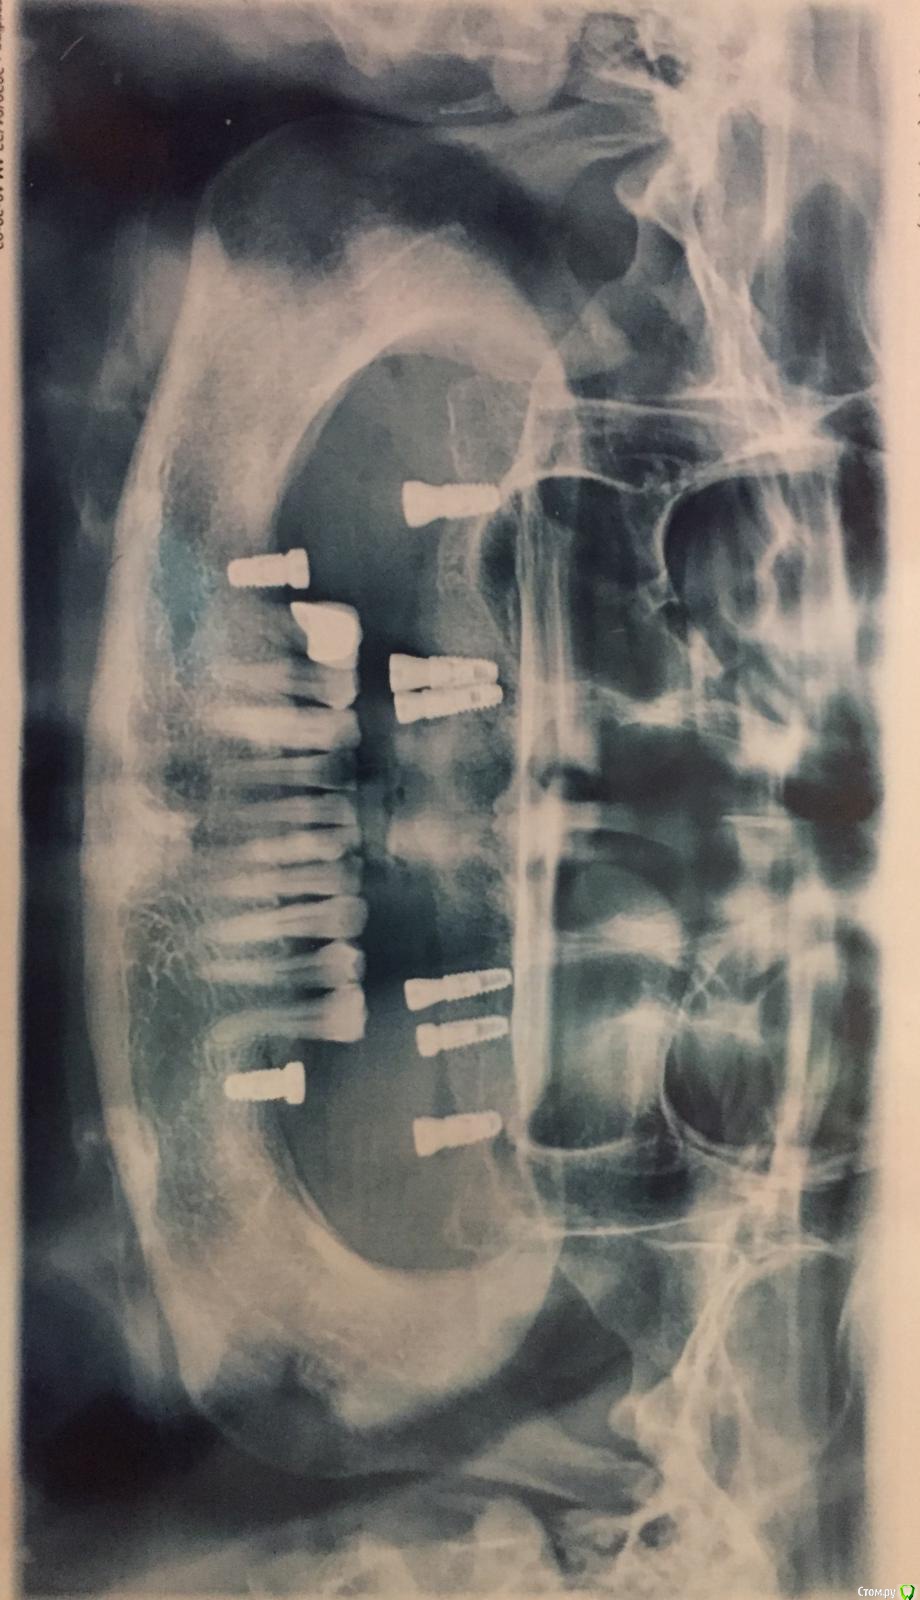

ALLA0105 Опубликовано 19 января, 2020 Автор Поделиться Опубликовано 19 января, 2020 (изменено) На нижней челсюти свои зубы/коронки,или пластмассовый протез?На нижней челюсти свои зубы с 35 по 45, на месте 36 и 46 тоже поставили импланты с формирователями. Мне кажется, что доктор на верхней челюсти поставил далеко импланты, где то 17 и 27 (это крайние). Схему установки имплантов доктор мне не обозначил. Это я сама так определила. М.б. мне для наглядности КТ сделать и выложить сюда ? Или панорамного снимка будет достаточно? Изменено 19 января, 2020 пользователем ALLA0105 Ссылка на комментарий

ALLA0105 Опубликовано 23 января, 2020 Автор Поделиться Опубликовано 23 января, 2020 Выложите ПанорамныйПрошу Вас прокомментировать. Ссылка на комментарий

chervoncevdaniil Опубликовано 24 января, 2020 Поделиться Опубликовано 24 января, 2020 Какая будет конструкция - понятия не имею Как так может быть,что вы платите деньги за установку такого количества имплантов и даже не представляете,что за конструкция будет в итоге? Если,например,она окажется по итогу съемной,вас этот момент не расстроит?Потому что при таком расположении имплантов несъемные протезы достаточно рискованы,тут как минимум просится еще один имплант спереди,да и справа,как подмечено выше лучше было бы поставить импланты не так близко.Наверное вам имеет смысл все таки переговорить с доктором,и желательно не с хирургом,кто эти импланты ставил,а с ортопедом,который на этих имплантах потом будет протезировать(если в вашей клинике это не один и тот же человек) и разобраться для себя что вам вообще будут по итогу ставить,потому что если вам сам дизайн конструкции не интересен,то хотя бы финансово то вы должны знать,сколько будет стоит протезирование,там ведь в зависимости от материалов и прочего разница может быть в цене в разы Ссылка на комментарий